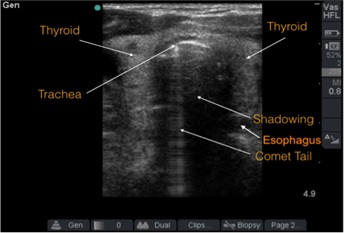

Para confirmar la ubicación del tubo endotraqueal mediante ultrasonido, primero hay que identificar la tráquea y el esófago (figura 1):

- Hay que usar un transductor lineal (mejor resolución para estructuras superficiales).

- El transductor se ubica en posición transversal sobre la tráquea, con el marcador hacia la derecha del paciente.

- Al ultrasonido, la tráquea se ve como una zona hiperecoica curva con una sombra posterior (“cola de cometa”).

- Luego, el esófago se encuentra distal y lateral a la tráquea (en la pantalla se va a ver a la derecha y un poco más abajo), se ve como una estructura oval hiperecoica con un centro hipoecoico.